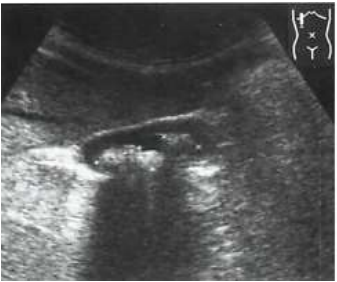

Qual artefato está representado na imagem a baixo: